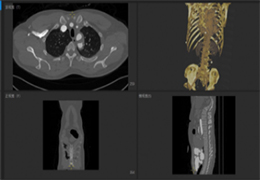

View X-Ray CT & MRI Scans Fast and Easily

FREE and easy to use 3D DICOM Viewer – for surgeons and patient education

Designed for surgeons, Pro Surgical 3D makes it easy to view patient scans quickly. Pro Surgical 3D facilitates the optimal 3D treatment and assessment workflows based on X-ray CT and MRI scans – and best of all, it’s FREE!

Everyone – including surgeons, patients and their loved ones – benefits from being better informed by the wealth of information buried within CT and MRI scans. Pro Surgical 3D gives surgeons more information to develop optimal treatment plans for patients. It also helps patients and their support group better understand their medical condition and proposed treatment options.

Traditional multi-planar slicing

High-quality and fast 3D reconstruction and 3D rendering

Performs 3D reconstruction and volume rendering.

Multi-planar slicing.

Oblique slicing.

Side-by-side comparative assessment for pre- and post-operative scans.